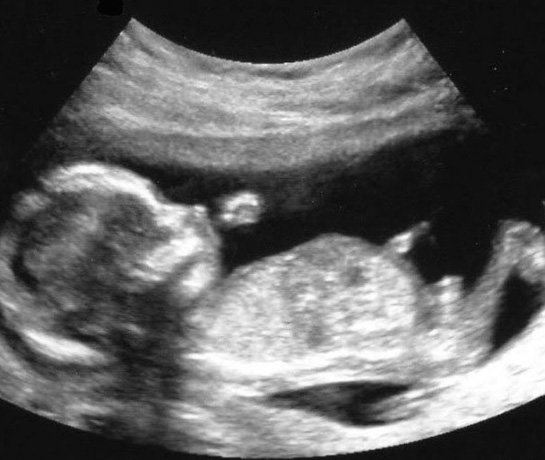

10 haftalık gebelik, hamileliğin ikinci trimesterine geçişin başlangıcını işaret eden önemli bir dönemdir. Bu dönemde, fetüs hızla gelişmekte ve anne vücudunda çeşitli değişiklikler meydana gelmektedir. Bu makalede, 10 haftalık gebeliğin fiziksel ve psikolojik etkileri, fetal gelişim, beslenme önerileri ve dikkat edilmesi gereken noktalar üzerinde durulacaktır. Fetal Gelişim 10. hafta itibarıyla fetüs, yaklaşık 3,5 cm uzunluğundadır ve bu haftada önemli gelişim aşamalarından geçmektedir. Aşağıda fetüsün bu aşamadaki gelişimsel özellikleri sıralanmıştır: